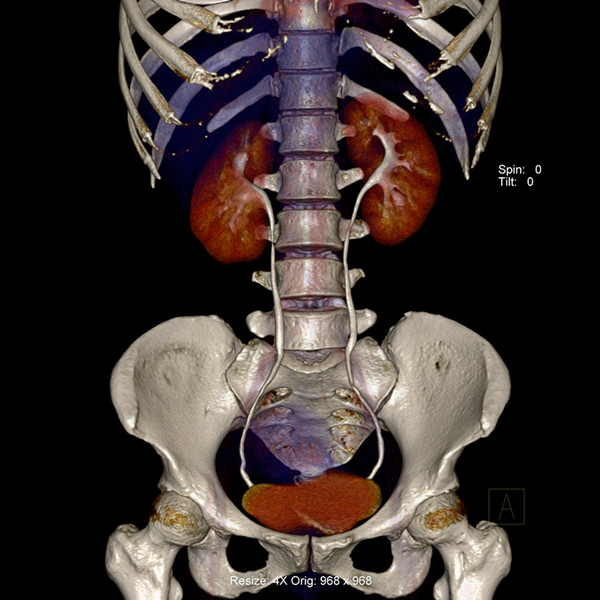

炫速雙源CT是目前世界上最先進的CT設(shè)備之一。它采用兩套64排圖像采集系統(tǒng),結(jié)合“飛焦點”技術(shù),并且有超高的旋轉(zhuǎn)速度,能夠在極短的時間內(nèi)完成掃描,為病人提供“綠色” CT 檢查。它的特點是炫速掃描技術(shù) (Flash Spiral),即大螺距的螺旋掃描,可以在一秒鐘之內(nèi)完成掃描,同時輻射劑量極低。 它的主要特色掃描技術(shù)如下:

純譜雙能 選擇性能譜純化技術(shù)(SPS)實現(xiàn)常規(guī)輻射劑量下的雙能量成像。憑借能譜純化技術(shù)以及獲得美國 FDA 上市許可的多項雙能量臨床應(yīng)用,第二代雙能量成像 將成為日常臨床應(yīng)用的完美選擇。

輻射敏感器官的射線保護 可自動屏蔽螺旋掃描中的無效輻射,并首次針對輻射敏感器官實現(xiàn)特異性輻射防護技術(shù)。  炫速雙源CT的適應(yīng)癥很廣泛,對心血管系統(tǒng)疾病的診斷幫助較大,是冠狀動脈疾病檢查的利器。適合于: